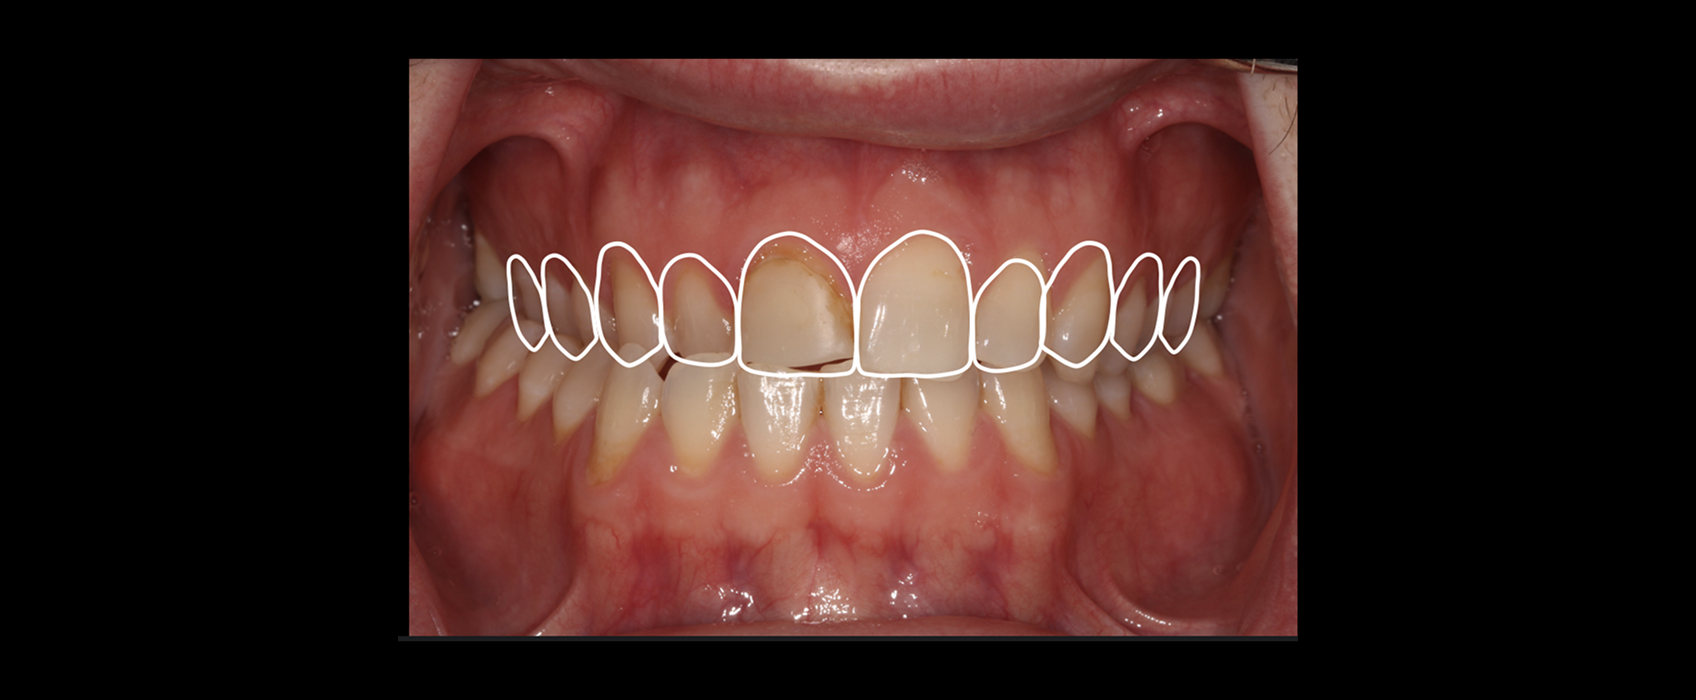

Zach, a patient in his mid-20s, came to our office seeking options for improving his upper front teeth, specifically the noticeable differences in size, shape, and shade between teeth #8 and #9. A childhood bicycle accident had left #8 chipped, and multiple composite restorations over the years hadn’t given him the esthetics he hoped for.

Taking an FGTP approach quickly revealed why restoring #8 had been so challenging. A crossbite was limiting available restorative space, and the gingival position of #8 was more coronal than #9, suggesting supereruption after the original trauma.

The more conservative and airway-conscious option was an orthodontic–restorative approach. Orthodontics could correct the crossbite, level the gingival margins, and restore harmony to the occlusal relationship.

Once the teeth were in their proper positions, we could address #8 and #9 with a single crown and veneer.